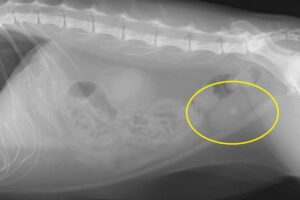

Rちゃんは丁度2年前、膀胱結石と尿路結石で尿路閉塞を起こし、膀胱切開と会陰部尿道瘻設置の手術を受けたオス猫君です。1年前のレントゲン撮影ではなかった膀胱結石が、今回ぽこんと1個見つかってしまいました。比較的大きいのと尿道瘻を作っているので、尿道に詰まることはないでしょうが…さて、困った!前回の結石の成分は「シュウ酸カルシウム」でした。これはなかなか厄介で、食餌療法をしていても予防が困難で、もうできる子は体質としか言いようがありません。今回は緊急性がないので、しばらく経過を見ることになりましたが困りました。

今年、膀胱結石を認める